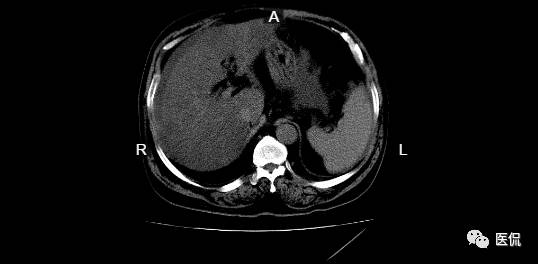

病例二

患者信息:男,57岁

检查部位:上腹部

检查方法:平扫

患者主诉:长期大量饮酒非常严重,现主要症状:全身颤抖,腹部发胀严重。

影像所见:

肝脏比例失衡,肝尾状叶变大,肝裂增宽,表面欠光滑,肝实质密度不均匀减低,CT值-3~9HU,肝脾包膜下见弧形水样密度影,CT值9HU;肝内外胆管无扩张,胆囊未见明显增大,壁不增厚;胰腺未见异常,脾脏增大,后余额63mm;腹膜后未见异常肿大淋巴结。

诊断意见:

肝脏改变、脾大、腹水:符合酒精性肝硬化改变。